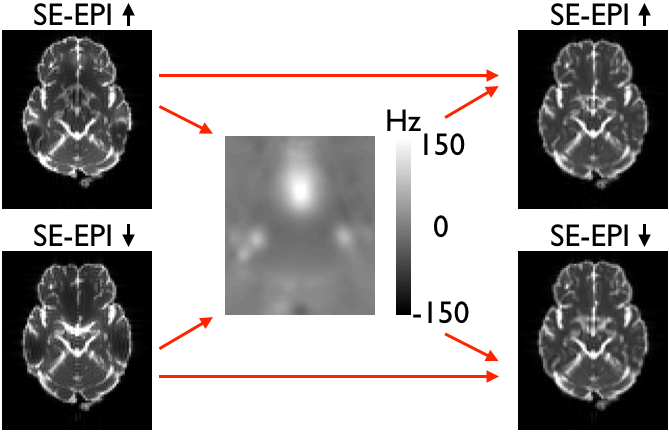

Below you see four examples of images acquired with different phase encoding. Below the images you see what you would find in the PDF protocol generated on a Siemens scanner for these acquisitions. Unfortunately I don't have enough experience of other scanner manufacturers to know where to find the information from those.

If you are uncertain about how to create your own --acqp file I suggest you get your scanner protocol, load your images into FSLVIEW and then find which of the images below that looks most like then one you have. When you have done that compare the "Phase enc." entry below that image with that in your protocol. When you are happy that you have found the right column you can use the three first values from the vector below the image.

Finally look up the "Echo spacing" and "EPI factor" entries in your Siemens protocol PDF and calculate the fourth column, the total readout time, from the formula

where \(S_E\) is the echo spacing in ms and \(F_{EPI}\) is the EPI factor.

| What you see in FSLeyes |

![]() |

|---|---|---|---|---|

| In Siemens protocol | Phase enc. dir P >> A Echo spacing 0.75 ms EPI factor 128 |

Phase enc. dir A >> P Echo spacing 0.75 ms EPI factor 128 |

Phase enc. dir R >> L Echo spacing 0.96 ms EPI factor 128 |

Phase enc. dir L >> R Echo spacing 0.96 ms EPI factor 128 |

| In --acqp file | 0 1 0 0.095 | 0 -1 0 0.095 | 1 0 0 0.122 | -1 0 0 0.122 |